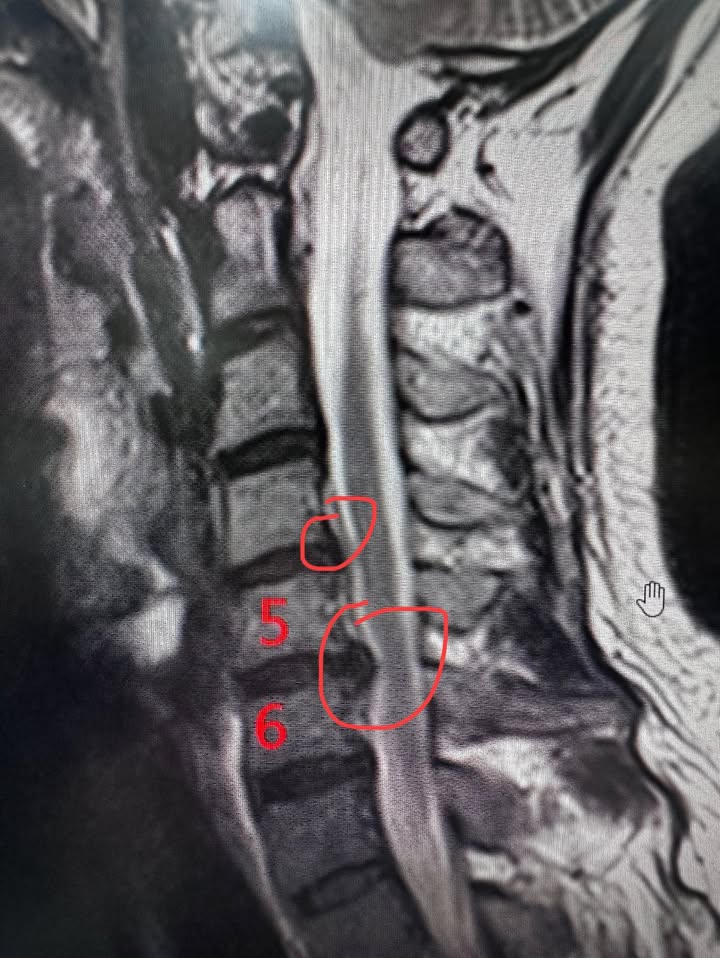

MRI的結果當天拍出來了!很明確——他的C5/C6頸椎神經根被壓迫,這是導致他疼痛和麻木的主要原因。我告訴他:「不需要開刀,我們可以用脊椎針刀微創療法試試。」他看著我,猶豫了一下,但還是點了點頭:「徐醫師麻煩你了,我信你。」